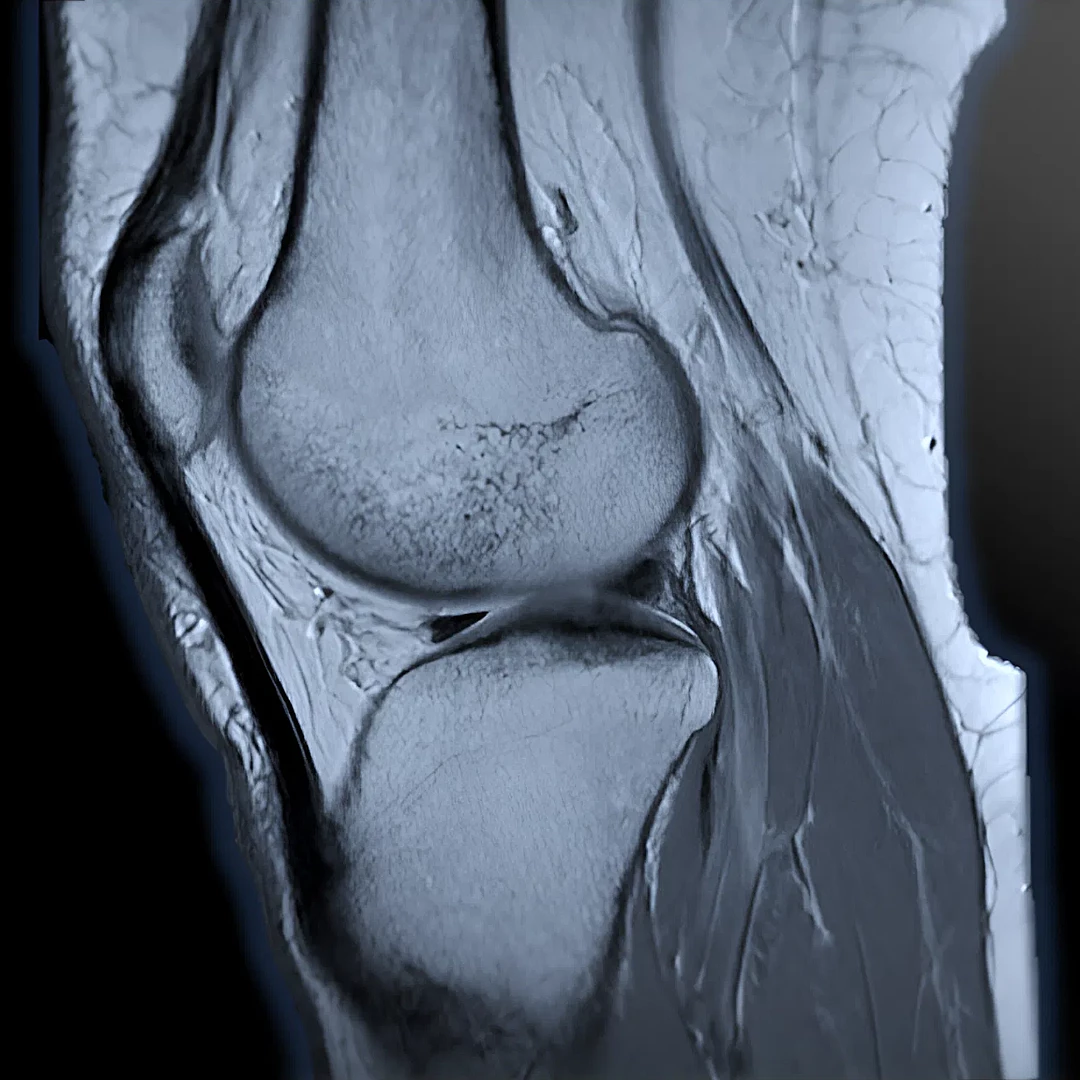

Advanced Joint and Bone MRI provides detailed imaging of joints, cartilage, and bones to assess injuries, arthritis, and degenerative conditions. It’s essential for accurate diagnosis and treatment planning in orthopedic and sports-related cases.